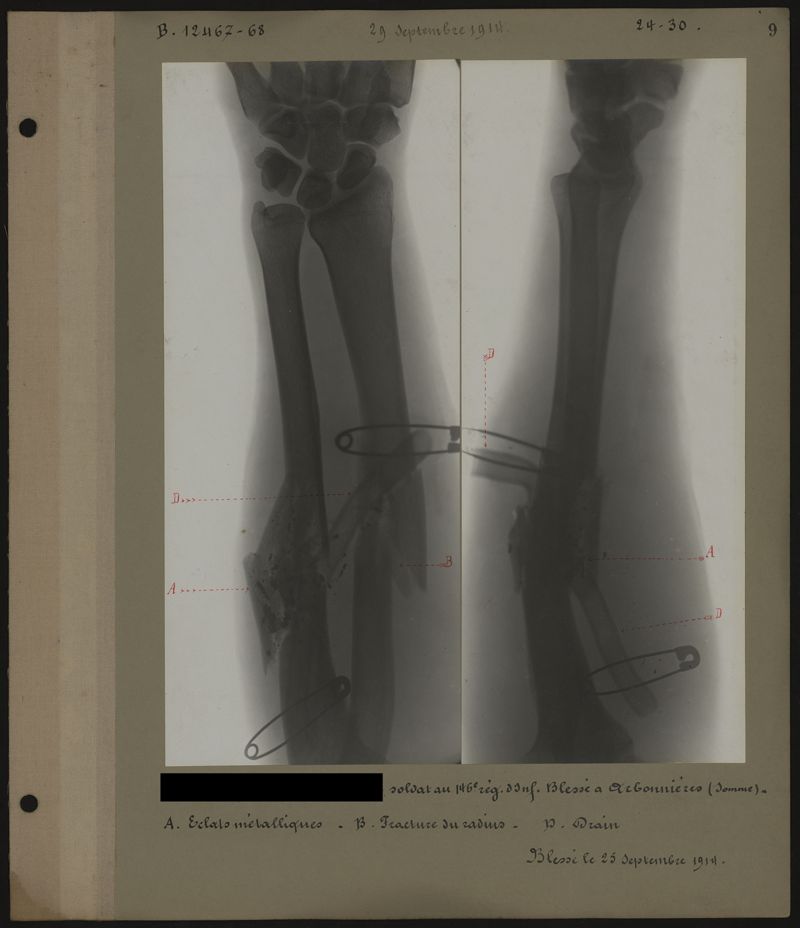

Deux albums de radiographies de la Première Guerre mondiale. Collection du laboratoire central de radiographie de la Salpêtrière. Premier album.

1914.